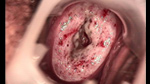

婦科leep錐切手術(shù) CIN2-3

CIN 2-3